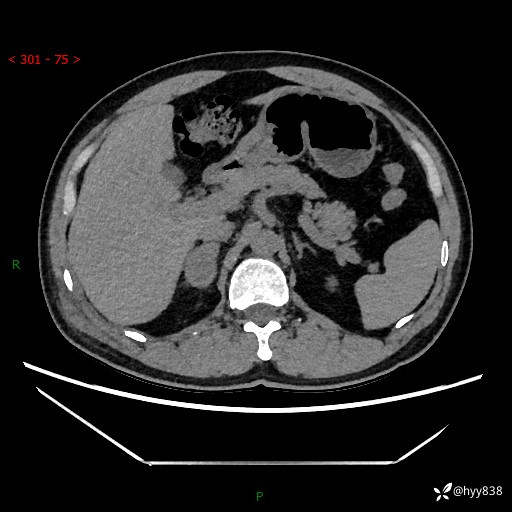

现病史:患者9月4日摔伤在深圳市宝安区中心医院行CT检查提示右侧肾上腺区结节(38*27mm),复查B超提示右侧肾上腺区可见一61*24mm异常低回声团,建议进一步检查。进一步完善增强CT后提示:右侧肾上腺区肿块及周围渗出改变,大致同前,考虑肾上腺腺瘤,不除外瘤内出血可能,否认阵发性头晕、头痛、出汗、乏力等不适,门诊以“ 右侧肾上腺肿瘤”收入住院。 起病来,患者精神、食欲、睡眠可,大便通畅,小便如上述,体力体重无明显改变。

肾上腺CT平扫

增强(动脉期+静脉期)